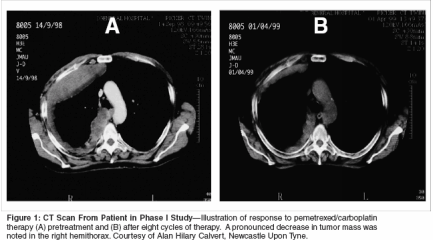

The combination of pemetrexedand carboplatin was evaluated in aphase I trial conducted by Hughesand colleagues.[17] Twenty-seven patientswith MPM received escalatingdoses of pemetrexed (400 mg/m2 to500 mg/m2) and carboplatin (AUC 4to 6). Pemetrexed was administeredas a 10-minute infusion and carboplatinwas administered as a 30-minuteinfusion, both on day 1 every 21 days.Pemetrexed at 500 mg/m2 and carboplatinat AUC 6 was the maximumtolerated dose; three of five patientsat this dose level experienced grade 4neutropenia as the dose-limiting toxicity.Nonhematologic toxicities at themaximum tolerated dose includednausea, vomiting, and stomatitis.There were no grade 4 nonhematologictoxicities reported at this doselevel. Two courses at all dose levelswere complicated by grade 3 elevationof transaminase levels. Responseto therapy was a secondary outcomeand was measured in all patients.Of the 25 patients evaluable forresponse, there were eight confirmedpartial responses, for an overall responserate of 32%. Five of the eightpatients who experienced partial responseshad stage IV disease, and fivepatients had mesothelioma of epithelialhistology. All of the patients whoreceived treatment with pemetrexedand carboplatin experienced cancerrelatedsymptoms at the start of chemotherapy.Nineteen (70%) of theoriginal 27 patients accrued experiencedrelief in cancer-related symptomswhile on study. Median overallsurvival was 451 days and mediantime to disease progression was 405days. Figure 1 shows the response ofa patient on this study. The recommendedphase II dose for this combinationwas determined to be pemetrexed500 mg/m2 and carboplatin AUC 5,which allowed for administration offull doses of both agents.Pemetrexed in CombinationWith Oxaliplatin